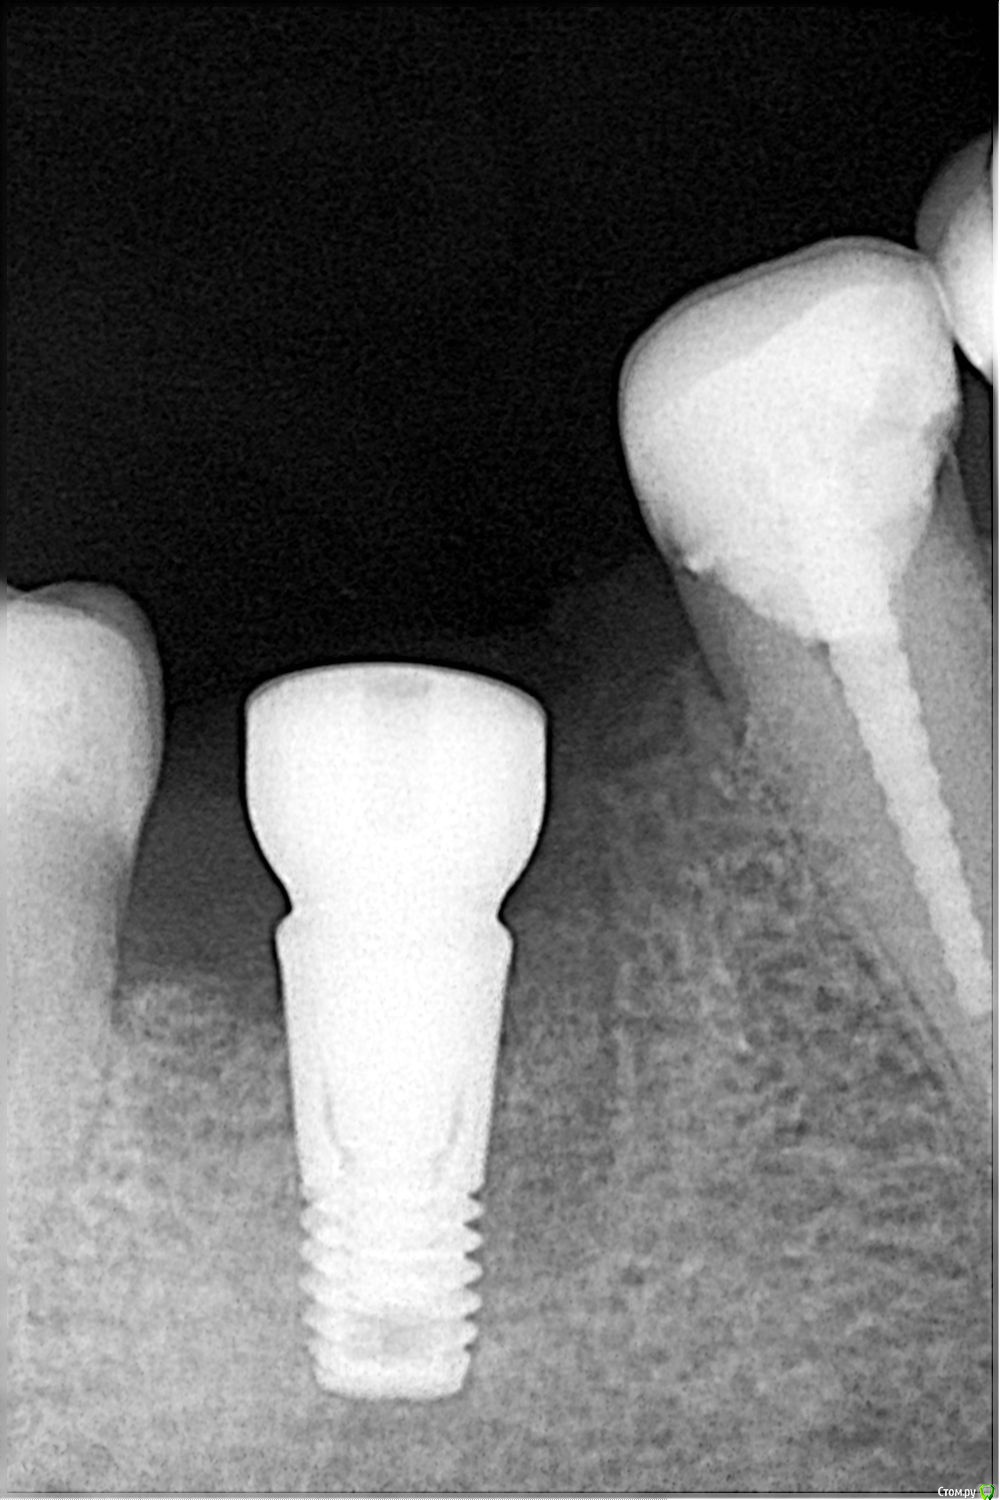

Nik-01 Опубликовано 11 марта, 2016 Автор Поделиться Опубликовано 11 марта, 2016 (изменено) сразу не разобралась как прикрепить фото. Сделан сразу после установки. Изменено 11 марта, 2016 пользователем Nik-01 Ссылка на комментарий